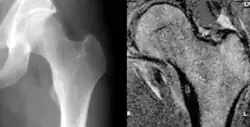

Osteoid osteoma of the lesser trochanter: X-ray and MRI with marked sclerosis around the nidus | |